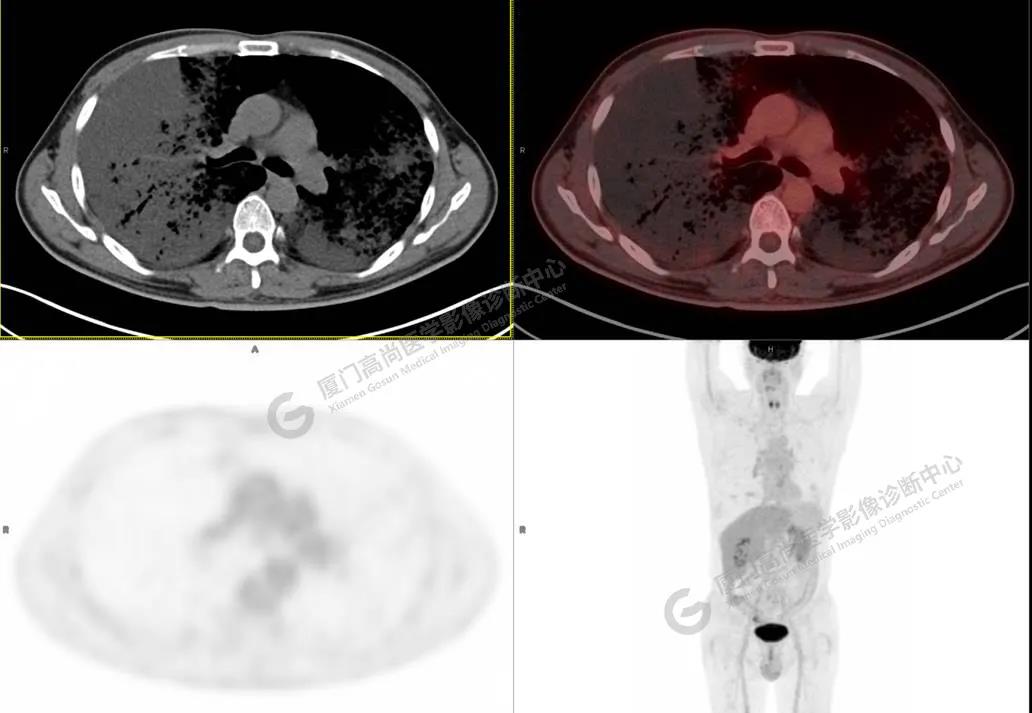

PET/CT影像圖

圖3

PET/CT所見(jiàn):雙肺大片實(shí)變影及磨玻璃影,部分呈地圖樣改變,累及右肺尖,部分放射性攝取輕微增高,SUVmax 1.77,其內(nèi)見(jiàn)多發(fā)支氣管充氣征象。

影像診斷: 雙肺大片實(shí)變影及磨玻璃影,大部分代謝不高,局部代謝輕微增高,考慮肺泡蛋白沉積癥,建議病理學(xué)檢查或肺泡灌洗物檢查。